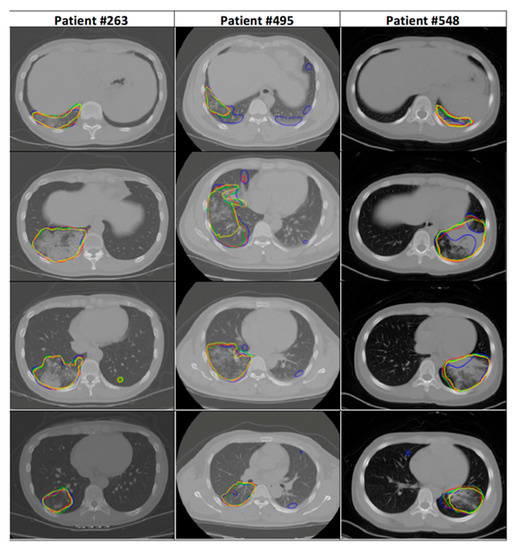

2.1. Dataset

- CT Images in COVID-19—The Cancer Imaging Archive (TCIA) Public Access—Cancer Imaging Archive Wiki. Available online: https://wiki.cancerimagingarchive.net/display/Public/CT+Images+in+COVID-19#702271074dc5f53338634b35a3500cbed18472e0 (accessed on 25 March 2021).

- Tsai, E.B.; Simpson, S.; Lungren, M.P.; Hershman, M.; Roshkovan, L.; Colak, E.; Erickson, B.J.; Shih, G.; Stein, A.; Kalpathy-Cramer, J.; et al. The RSNA International COVID-19 Open Radiology Database (RICORD). Radiology 2021, 299, E204–E213. [Google Scholar] [CrossRef]